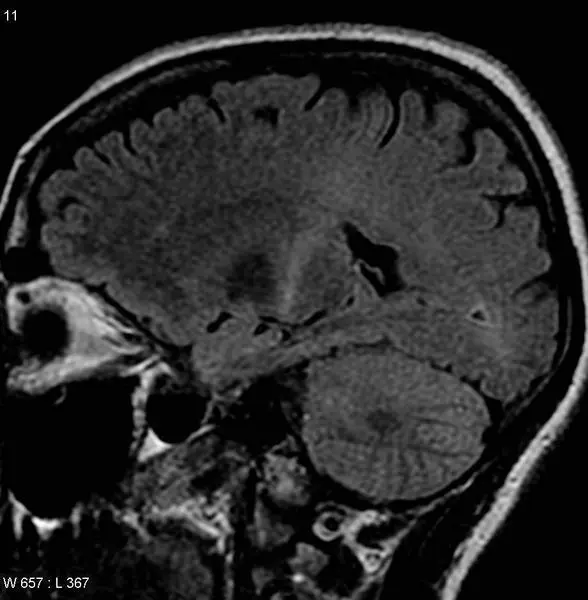

<p> Cerebro afectado por la ELA </p>

Cerebro afectado por la ELA